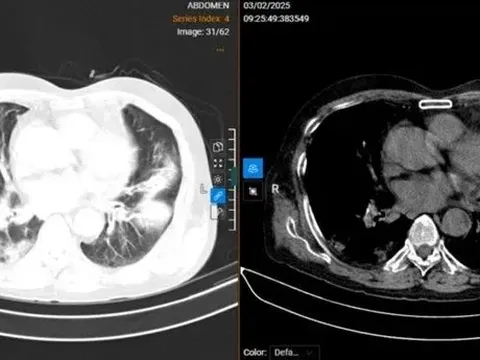

Một bệnh nhân biến chứng cúm A khiến phổi trắng xóa

Bệnh nhân ở Vĩnh Phúc mắc cúm A phải duy trì thở oxy để hỗ trợ hô hấp.

11:39 17/02/2025